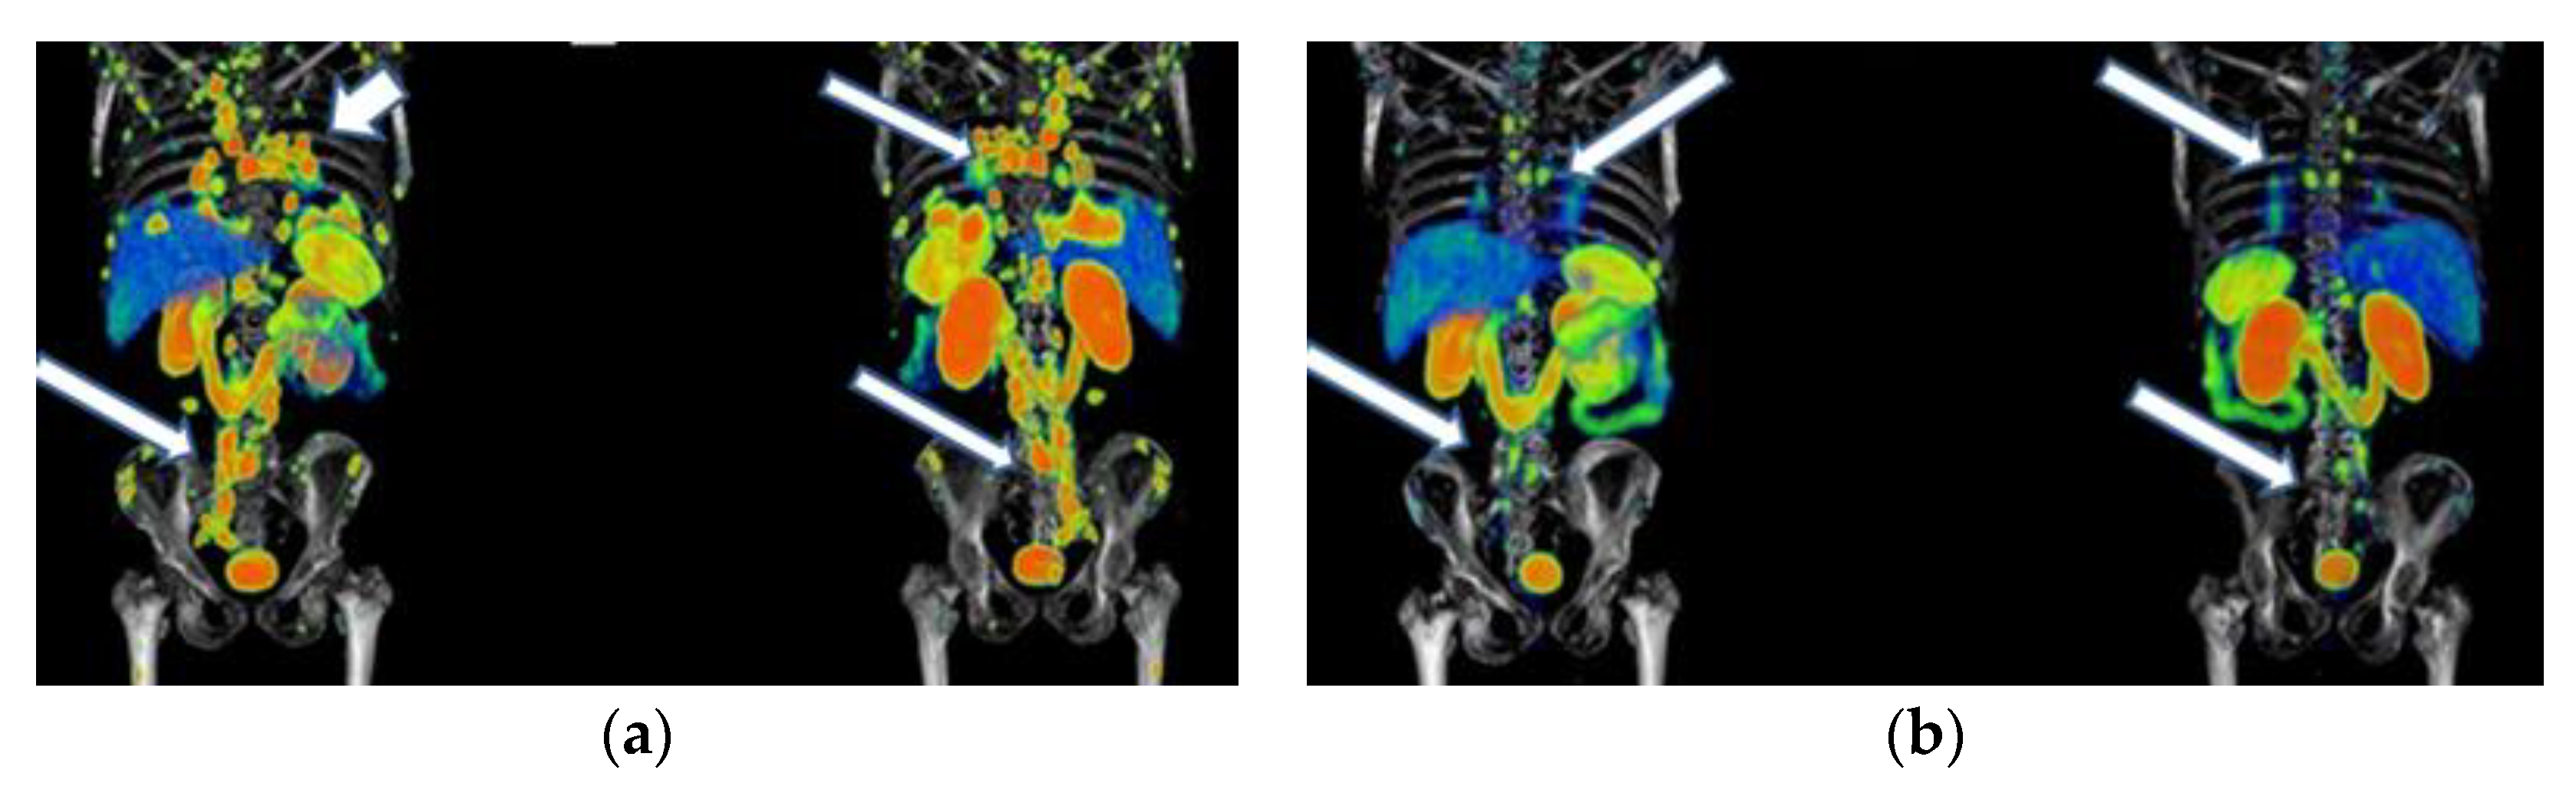

Figure 8. A 76-year-old female patient received four doses of 177Lu-DOTATOC with stable disease as determined by 68Ga-DOTATOC PET/CT imaging. Findings: 11% overall increase in somatostatin receptor expression in the primary pancreatic tumor lesion, as well as metastatic deposits in lymph nodes, liver, and peritoneal implants toward the root of the mesentery, jejunum, and pelvic cavity, without significant morphologic changes. Data refer to a stable disease. (a) 68Ga-DOTATOC PET/CT imaging before 177Lu-DOTATOC therapy, (b) 177Lu-DOTATOC SPECT imaging (first dose), (c) 68Ga-DOTATOC PET/CT imaging ten months after the first dose of 177Lu-DOTATOC.

Figure 6, Figure 7 and Figure 8 show typical clinical cases of partial response and stable disease after 177Lu-DOTATOC therapy (the stable disease does not meet the criteria for partial response or progressive disease).

177Lu-iPSMA therapy is a convenient option for the treatment of multiple metastases and large tumor lesions (Appendix A) (Figure A1, Figure A2 and Figure A3). For example, in the case shown in Figure A1, the patient suffered from severe pain characteristic of the terminal stage of the disease. However, two weeks after administration of the first dose of 177Lu-iPSMA, the subject showed relevant pain relief. Furthermore, after administering four doses of 177Lu-iPSMA (four doses of 7.4 GBq), metastatic lesions in the hip and spine were significantly reduced, prolonging the patient’s life for 19 months after therapy. In this context and based on the results of this study, 177Lu-iPSMA therapy should be considered and evaluated in future clinical trials as a second-line rather than third- or fourth-line therapy in patients with mCRPC, with the potential to improve patient survival.

Figure A1. Patient with mCRPC who had a partial response to 177Lu-iPSMA treatment: (a) anterior and posterior 68Ga-iPSMA imaging before 177Lu-iPSMA treatment, and (b) after 177Lu-iPSMA therapy (four doses of 7.4 GBq). Arrows indicate tumor lesion sites.